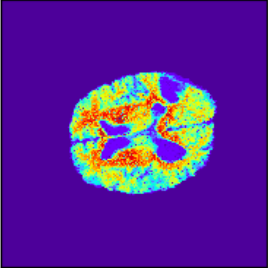

(e) Uncertainty

(j) Uncertainty

Figure 3: Intra and Inter modality MR registration. Time taken: 0.21 sec

To illustrate the performance of the proposed technique for clinical applications, MR images were chosen. The performance of the technique was tested by registering multi-modal MR image pairs. In a clinical setup, it is common practice to register images or volumes acquired from different imaging modalities or MR sequences. Figure 3 illustrates the degree of overlap between moving images (a) T2 and (f) T1 weighted sequence on fixed images (b) T2 and (g) T2 weighted sequence respectively. It was observed using the registration proposed in this manuscript, the dice score improved from 0.44 (prior to registration) to 0.91 (post registration) for multimodal sequences. On the BraTs data, figure 4 (a-d) illustrates the performance of our method based on other metrics such as Dice, SSMI, MI, and MSE respectively. As the key points were generated by utilizing only the feature maps of the initial two layer of the network, the spatial dimension of the data has little impact on the performance. Unlike other CNN based technique which considers the entire image for estimating the transformation parameters, our method requires CoMs which reduces the dimensionality from (m ×\times n ×\times n) to (m ×\times 2), where m denotes the number of feature maps and n is the pixel dimension of the feature map. This aids in lowering execution time drastically. The proposed pipeline also consists of an uncertainty estimator. uncertainty maps illustrated in all the above examples show the region of higher variance in registration, which in turn suggests surgeons/ observers to make better decisions. Pixel region with red color indicates the larger variance region while blue indicated low variance region. For example in figure 3 (e) shows that the central region of the brain has higher pixel-wise variance as compared to the outer part of the brain. The performance of the algorithm on volumes on the same modality is illustrated in figure 3 (a-e)